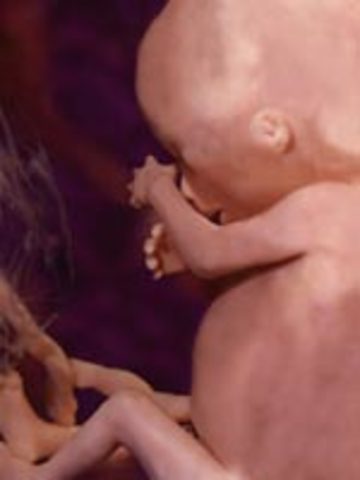

The fetus has most likely turned to a head down position in preparation for birth. The baby is developing immunities to mild infections.

FUN FACT: The child now has an excellent chance of survival outside the womb.

The fetus is ready for birth and is settling into the fetal position with its head down against the birth canal.

FUN FACT: By now all systems are developed and ready to go.